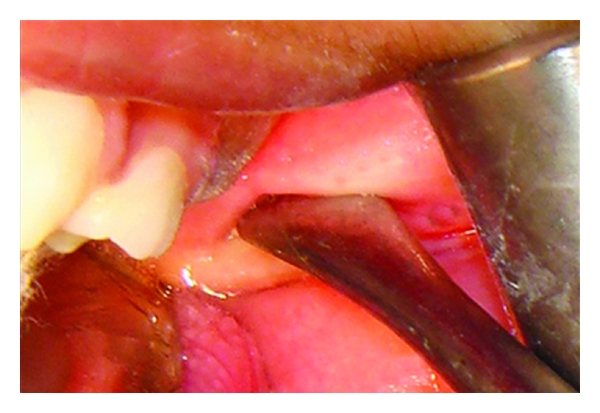

Surgical procedure for excision of the bony mass was performed under general anesthesia. The bony mass was palpated, and a vertical mucosal incision was given over it. Blunt dissection was performed to expose the bony mass (Figure 6). The bony mass was easily separated from the surrounding tissues and removed in toto (Figure 7). The fibrous tissue adjacent to the mass was excised. Hemostasis was achieved, and site was closed with 3–0 vicryl. Postoperative period was uneventful. 3 years postoperatively patient showed adequate mouth opening (Figure 8). Histopathologic examination of the mass revealed presence of mature lamellar bone.